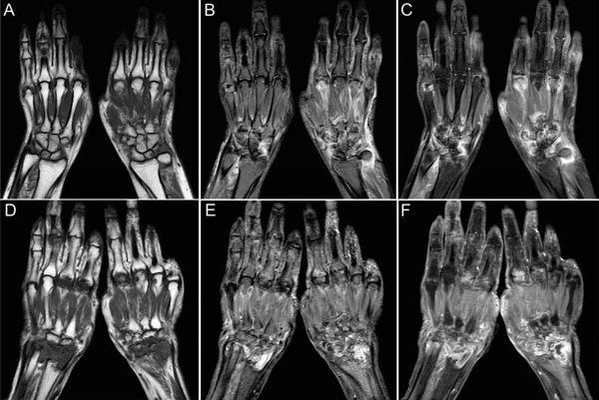

Ревматоидный артрит поражает людей молодого возраста. Начинаются симптомы с мелких суставов кистей рук, стоп. МРТ руки следует сделать, так как можно заметить минимальные изменения в суставах: неровность контуров хряща, сужение щели или наоборот, выпот внутри сустава. Такие изменения вместе с лабораторными признаками позволяют поставить диагноз и начать лечение, пока больной не испытывает сильных болей, скованности, большинство суставов имеют нормальную структуру. Раннее лечение значительно улучшает качество жизни таких больных, предупреждает наступление множественных деформаций суставов и инвалидности.